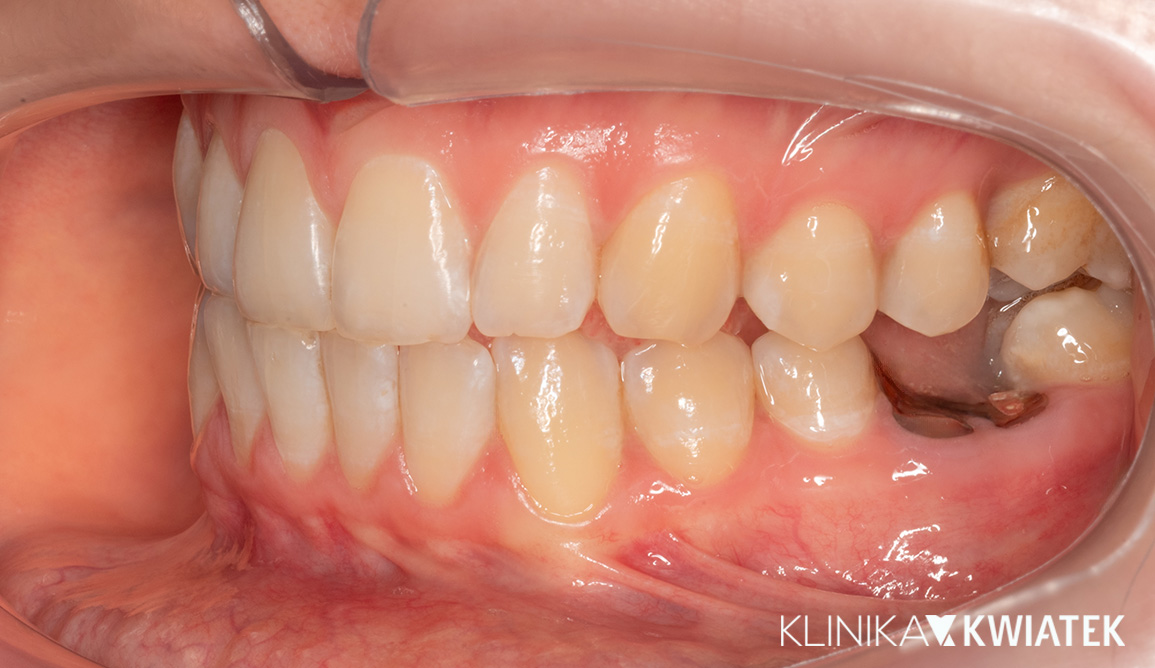

Kliniczna precyzja i estetyka – jak przywróciliśmy funkcję i piękno uśmiechu

Pacjentka zgłosiła się z wadą zgryzu, licznymi ubytkami i utraconymi zębami trzonowymi, co powodowało trudności w żuciu i estetyczne niezadowolenie. Leczenie obejmowało ekstrakcje, ortodoncję, implantację oraz kompleksową rekonstrukcję protetyczną. Po kilkunastu miesiącach terapii Pacjentka odzyskała pełną funkcję zgryzu i piękny, harmonijny uśmiech.